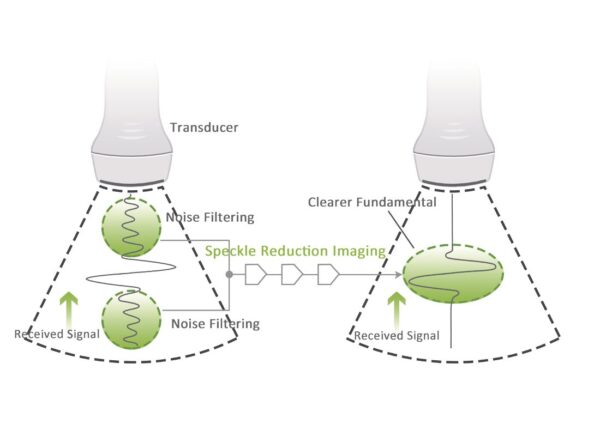

Advanced Imaging Optimization Technology